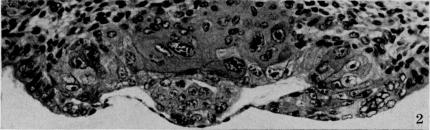

On the development of the amnion and exoccelomic membrane in the previllous human ovum.

Yale J Biol Med. 1945 Dec;18(2):107-15.